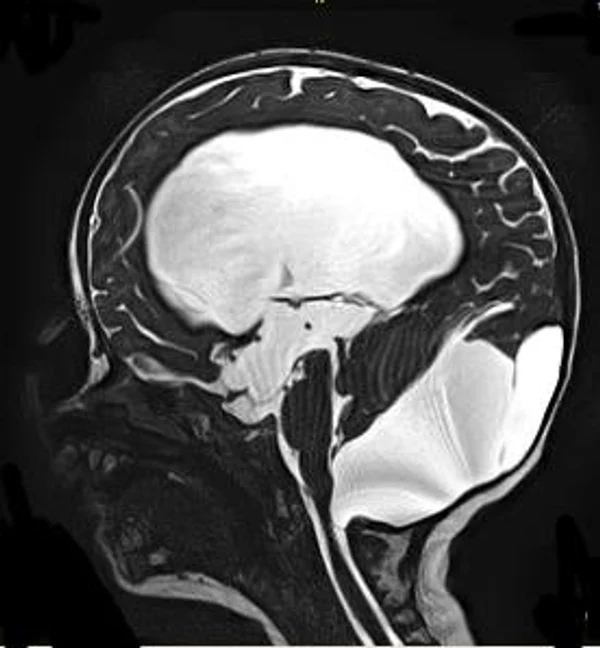

кисты, аномалии Денди-Уокера и др.Операции при внутричерепных кистах. В основном встречаются арахноидальные кисты различных локализаций и кисты сосудистых сплетений боковых желудочков. Пациентам с врождёнными кистами операции проводятся в следующих ситуациях: увеличении объема кисты в динамике, наличии клинических проявлений, компрессии и дислокации мозговых структур, наличии окклюзии ликворных путей. Нами используются 2 способа хирургического лечения кист: эндоскопическая перфорация стенок кист и открытая резекция кист. Открытая резекция кист проводится при ретроцеребеллярных арахноидальных кистах (рис. 2), при арахноидальных кистах межполушарной щели при отсутствии непосредственного контакта их стенок со стенками расширенных желудочков головного мозга и повторного увеличения кист средней черепной ямки после эндоскопической кисто-цистерностомии. Техника операции заключается в проведение краниотомии и максимальном иссечении стенок кист с созданием широкого сообщения кист с субарахноидальным пространством. Эндоскопические операции проводятся при арахноидальных кистах межножковой и пинеальной цистерн, арахноидальных кистах межполушарной щели при тесном контакте их стенок со стенками расширенной желудочковой системы (рис. 3), первично при арахноидальных кистах средней черепной ямки, а также при кистах сосудистых сплетений боковых желудочков. При арахноидальных кистах межножковой цистерны эндоскопически проводится перфорация стенок кисты, сообщая ее с просветом III желудочка и межножковой цистерной – эндоскопическая вентрикуло-кисто-цистерностомия (рис. 4). При арахноидальных кистах пинеальной цистерны проводится перфорация кисты в передне-верхних её отделах с созданием сообщения полости кисты с просветом III желудочка – эндоскопическая кисто-вентрикулостомия. С целью предотвращения облитерации сформированного отверстия иногда в полость кисты под контролем эндоскопа вводится стент перфорированный на протяжении (рис. 5, 6). Эндоскопическая кисто-цистерностомия выполняется при арахноидальных кистах средней черепной ямки. При этом создается широкое сообщение кисты с базальными цистернами. При кистах сосудистых сплетений боковых желудочков проводится их вскрытие в просвет боковых желудочков – эндоскопическая кисто-вентрикулостомия. При множественных кистах проводится их хирургическое сообщение между собой – интеркистосмия